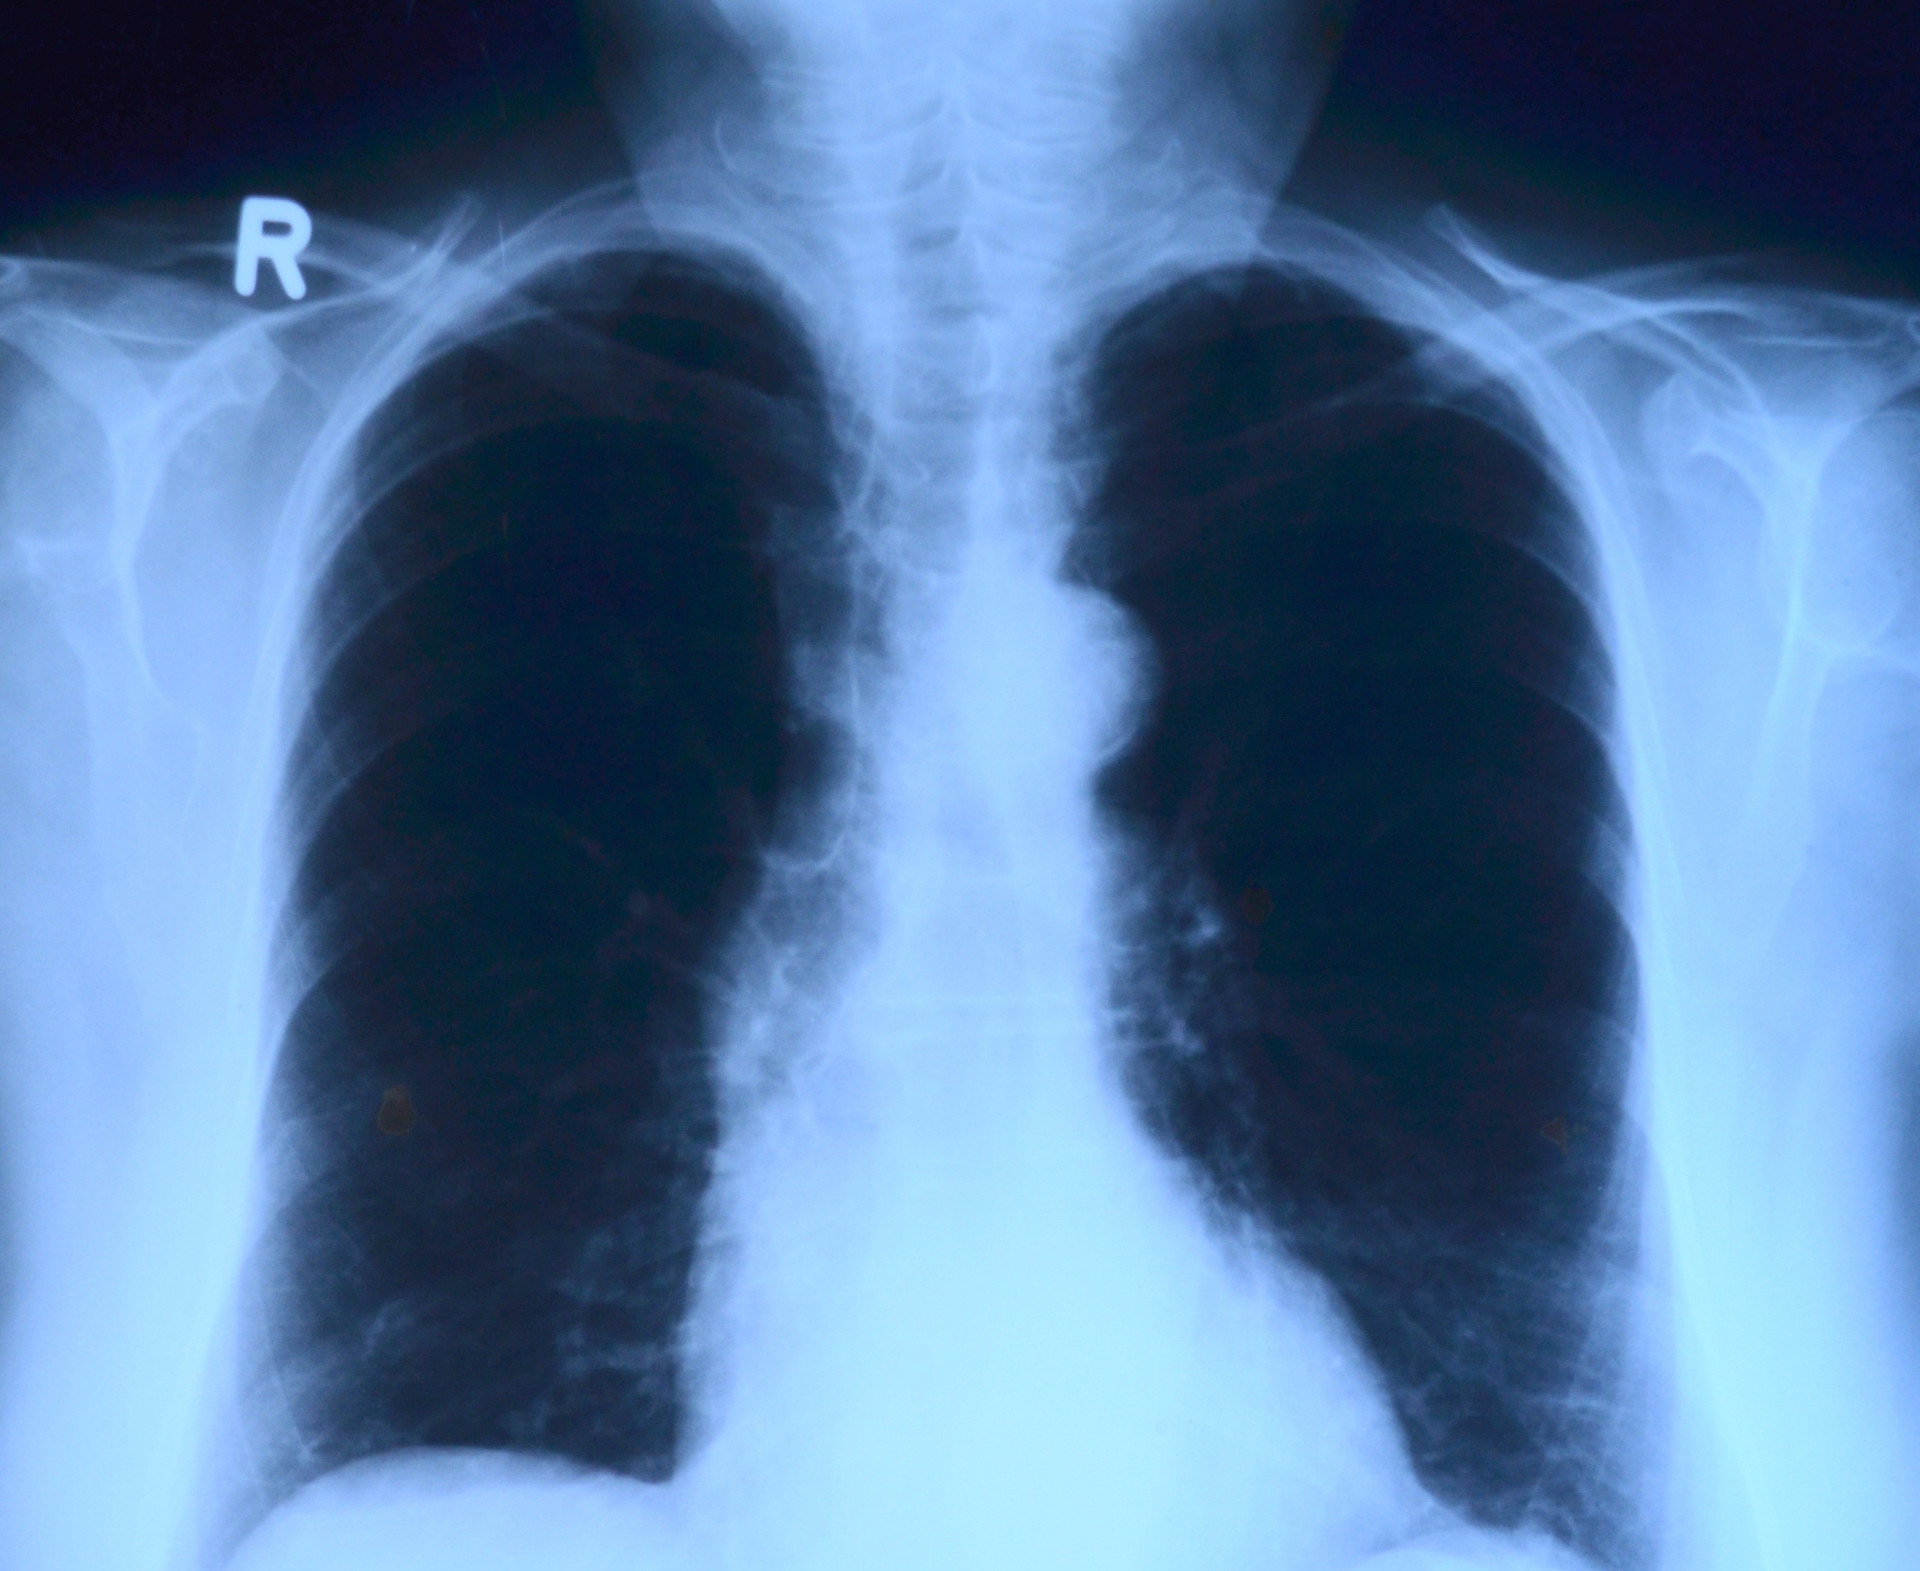

Ежегодно услугами местных рентгенологов пользуются более 5  тысяч пациентов Фото: pxhere 1920 1571 true 1571 1571 true 1920 1440 true 1920 1080 true

Рентгенохирургия развивается в  краевой больнице уже  20  лет. Ежегодно здесь обследуются более 5  тысяч пациентов и  выполняется не  менее 6  тысяч ангиографических исследований и  4,5 тысяч рентгенэндоваскулярных операций.